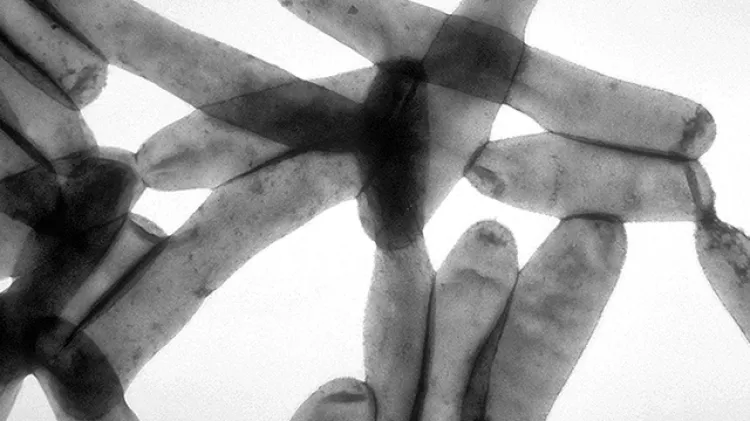

Omar ChiqueteNuevo Día / Nogales, ArizonaMientras cientos de miles de trabajadores fueron enviados a casa y los edificios de oficinas fueron evacuados por preocupaciones sobre el Coronavirus, los Centros de Control de Enfermedades (CDC), advierten sobre un posible problema de salud secundario cuando regresen: la enfermedad del legionario.Los CDC reconocen que están lidiando con el descubrimiento de una bacteria en algunos de sus edificios alquilados en el área de Atlanta. Varios edificios ahora están cerrados porque se encontraron bacterias en su sistema de agua, probablemente debido al cierre prolongado.“Durante los recientes cierres en nuestro espacio alquilado en Atlanta, trabajando a través de la Administración de Servicios Generales (GSA), los CDC ordenaron al propietario que tomara medidas de protección”, dijo el CDC en un comunicado a CNN .“A pesar de sus mejores esfuerzos, se notificó a los CDC que la bacteria “Legionaria”, puede causar la enfermedad del legionario, está presente en una torre de enfriamiento de agua, así como en algunas fuentes de agua en los edificios. Por precaución, hemos cerrado estos edificios hasta la remediación exitosa este completa “.La bacteria crece en agua tibia o estancada, por lo que existe preocupación porque los edificios de oficinas y los restaurantes quedan abandonados durante la pandemia. La bacteria es común en el agua y, por lo general, sólo es un problema cuando el agua se aerosoliza y la gente la inhala; las fuentes comunes son duchas y fuentes de agua. La bacteria Legionella puede causar una neumonía mortal. El año pasado, informan los CDC, se reportaron cuatro 294 casos. En lo que va del año, se han reportado mil 813 casos.No se sabe si los cierres provocados por la pandemia empeorarán el problema o lo mejorarán; la gente no se está reuniendo tanto en hoteles, oficinas o edificios de fábricas; sin embargo, miles de kilómetros de tuberías en los edificios están vacíos y estancados en los cálidos meses de verano.“Actualmente no existe una vigilancia nacional de los sistemas de agua para detectar la enfermedad de Legionella”, dijo a CNN Chris Edens, epidemiólogo del equipo de Legionella de los CDC. Dijo que los departamentos de salud estatales que normalmente monitorean y reportan casos de infección por Legionella están atados a lidiar con el Coronavirus.Para reducir la probabilidad que las bacterias crezcan en las tuberías, mantenga el agua fría muy fría y el agua caliente muy caliente; la bacteria Legionella crece entre 80 ° y 120 ° Fahrenheit.El CDC tiene recomendaciones en su sitio web para que los propietarios de edificios vuelvan a abrir después de un cierre prolongado.